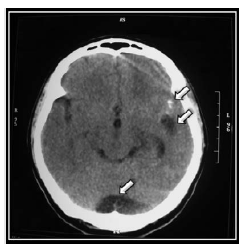

Eleven days after admission, a second brain CT showed supratentorial hydrocephalus, megacisterna magna and three scattered calcifications in both cerebral hemispheres (Figure 1 and 2).